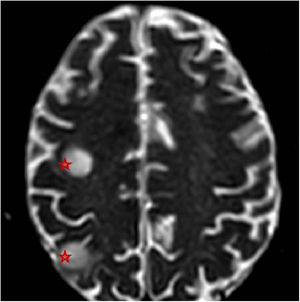

Pasados dos meses del último ingreso, acudió a urgencias por radiculopatía refractaria a analgesia convencional y pérdida de fuerza en miembros inferiores, destacando a la exploración paresia flácida de ambos miembros inferiores (0/5) y del miembro superior derecho (2/5). La resonancia magnética reveló múltiples lesiones ocupantes de espacio (12 en total) en territorio infra y supratentorial (fig. 1), así como un absceso intramedular a nivel C5–C6 (fig. 2).